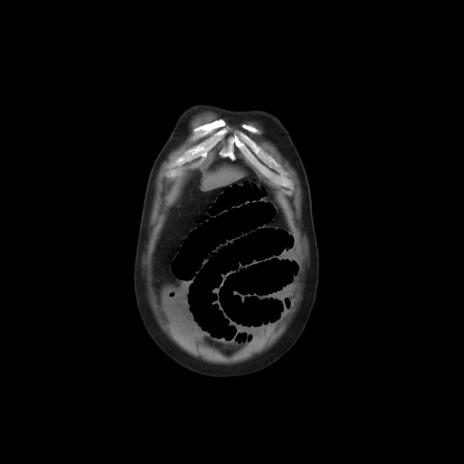

症例20(冠状断像)

【症例】 60歳代男性

【主訴】 腹部膨満、嘔吐

【現病歴】5日前頃より倦怠感を認め食事量減少し4日前の朝嘔吐、食事摂取困難となった。 3日前近医受診し点滴施行され整腸剤などを処方された。 当日他院を受診し、腹部膨満著明、炎症反応の上昇(CRP10.8、WBC11200)あり、紹介受診となる。

【身体所見】 意識JCS1 受け答えがはっきりしないBP 111/57mHg、 P 67bpm、、BT35.2°C、SpO2 97%(RA)、 腹部:膨隆、打診で鼓音あり、全体的に圧痛有り、腸蠕動音(-)、反跳痛ははっきりせず。

【データ】WBC 11400、CRP 14.20

矢状断像